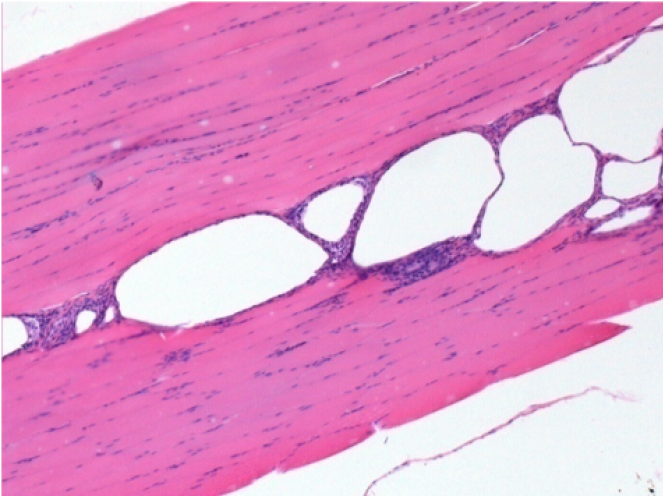

10 days after Endopeel Injection

10 days after Endopeel Injection 0.1ml in the right pretibial muscle.

Here you may see the formation of the vacuoles which are surrounded by lymphocytes. Vacuoles are different from tissue necrosis . The presence of lymphocytes is related to the permeability of the cell membranes.

L : Control-100xD10

R:100xD10

R :200xD10

R :400xD10